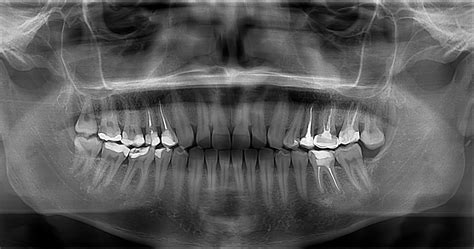

Quiste dental en radiografía.

El diagnóstico de un quiste dental se basa en la correlación de hallazgos clínicos, radiográficos e histopatológicos. En etapas iniciales, muchos quistes periapicales son asintomáticos y se detectan incidentalmente en radiografías de control (por ejemplo, en una radiografía panorámica de rutina, aparece como un área radiolúcida alrededor de la raíz de un diente). Cuando crecen, pueden manifestarse con expansión lenta de la cortical ósea, palpable como una tumefacción indolora en la encía o mandíbula.

Típicamente, en las radiografías los quistes odontogénicos aparecen como radiolucideces uniloculares bien delimitadas, a menudo con un borde esclerótico radiopaco fino que indica una respuesta ósea reactiva. En un quiste periapical clásico, la imagen radiográfica muestra una zona oscura redondeada alrededor del ápice de la raíz involucrada, que puede desplazarse o confluir con las raíces adyacentes.

Las técnicas radiográficas son esenciales para la evaluación diagnóstica. La radiografía periapical intraoral permite visualizar detalles de lesiones alrededor del ápice dental, mientras que la radiografía panorámica ofrece una visión general de ambos maxilares, útil para identificar lesiones quísticas extensas o múltiples.